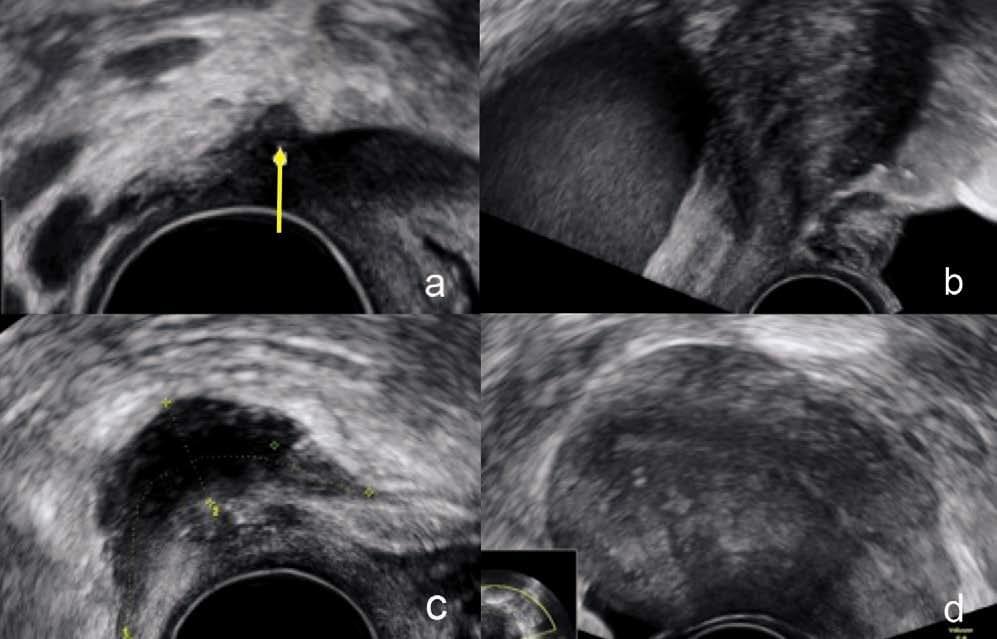

Transvaginaler Ultraschall: Unser wichtigstes Instrument

Das Herzstück unserer Diagnostik ist die hochspezialisierte transvaginale Ultraschalluntersuchung. Damit können wir die Gebärmutter, die Eierstöcke und die gesamte Region des kleinen Beckens praktisch direkt erreichen und im Detail einsehen.

Im Gegensatz zu statischen Verfahren ermöglicht uns der Ultraschall eine dynamische Beurteilung:

- Organbeweglichkeit: Wir können direkt erkennen, wie die Organe gegeneinander gleiten oder ob Verwachsungen die natürliche Beweglichkeit einschränken.

- Druckschmerz-Identifikation: Durch gezielten Kontakt mit der Ultraschallsonde können wir schmerzhafte Regionen lokalisieren. Diese Informationen sind für eine verlässliche Diagnose der Endometriose von grosser Wichtigkeit und können für weitere Therapieentscheidungen sehr wichtig sein.